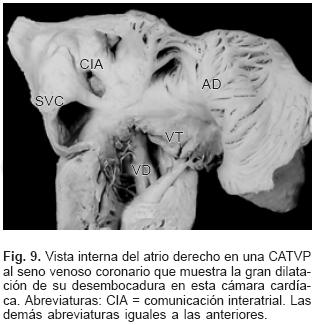

En la CATVP al atrio derecho el SVP se integra en la parte posterosuperior de esta cámara a través de un colector muy corto (Fig. 7). En el sitio de conexión al seno venoso coronario el colector venoso desembocó en el extremo izquierdo de dicho seno el cual estuvo dilatado (Figs. 2 y 8). El orificio de desembocadura del seno venoso coronario en el atrio derecho fue muy amplio y se situó por debajo de la comunicación interatrial (Fig. 9). En un espécimen existió estrechez intrínseca del colector en el sitio en que se unió al seno venoso coronario. En la conexión anómala infradiafragmática el SVP recibió las venas de ambos pulmones y se continuó con un colector largo que acompañó al esófago, atravesó el hiato esofágico y descendió hasta desembocar en la vena porta justo antes de penetrar al hígado (Fig. 10). Todos los corazones de este grupo presentaron obstrucción extrínseca a nivel del hiato esofágico y en dos especímenes se agregó obstrucción intrínseca en el colector antes de su desembocadura en la vena porta (Fig. 10).

En el grupo mixto el trayecto de los colectores provenientes de cada pulmón dependió de los sitios de conexión anómala (Tabla II). Los setenta y tres corazones en situs solitus e inversas presentaron un defecto septal interatrial de tipo orificio oval (Figs. 2, 4, 7 y 9), mientras que en los treinta corazones con dextroisomerismo existió un atrio común y una bandeleta septal interatrial que separó dos grandes comunicaciones (Fig. 11). Todos los corazones presentaron dilatación de las cámaras derechas, del tronco y ramas de la arteria pulmonar así como hipertrofia del ventrículo derecho (Fig. 12). Respecto a las cámaras izquierdas el atrio fue pequeño e incompleto por carecer del SVP (Fig. 2), el ventrículo izquierdo y la válvula mitral tuvieron características normales. Las cardiopatías asociadas en los setenta y seis corazones con situs solitus e inversus se consignan en la Tabla III. Los treinta corazones con dextroisomerismo presentaron un patrón complejo de asociación de anomalías intracardíacas y vasculares (Tabla IV); en las Tablas V y VI se muestran respectivamente los tipos de conexión atrioventricular y ventriculoarterial en dextroisomerismo.